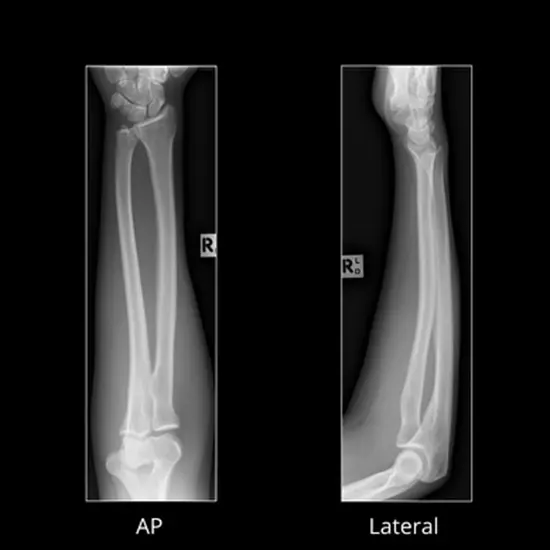

X-ray Right Arm AP & LAT

The X-ray Right Arm AP Lat test is a painless, safe way to see the forearm's bones, skin, and muscles.